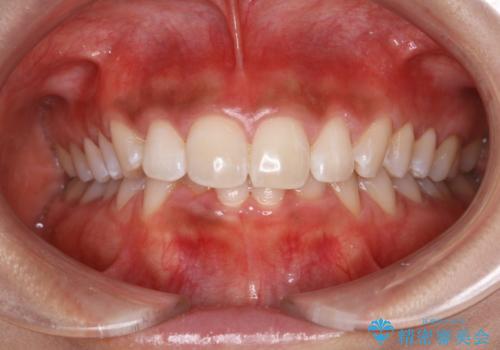

- 1か月後に結婚式があるため、歯を白くしたいとのことでした。

オフィスホワイトニング(TION Whitening・処置前クリーニング込み)コースを行いました。

ご希望の自然な白さに、トーンアップしたとのことで満足していただけました。